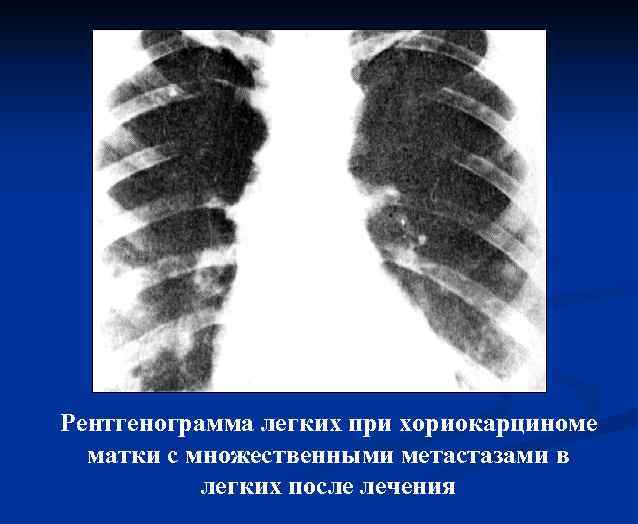

Рентгенологические методы исследования Рентгенограммы легких при хориокарциноме матки с множественными метастазами в легких

Рентгенограмма легких при хориокарциноме матки с множественными метастазами в легких после лечения